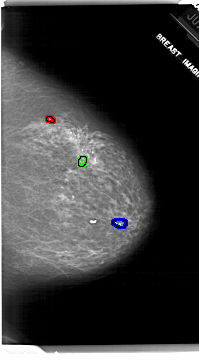

FILE: A_1917_1.RIGHT_MLO.OVERLAY

TOTAL_ABNORMALITIES 1

ABNORMALITY 1

LESION_TYPE CALCIFICATION TYPE DYSTROPHIC DISTRIBUTION CLUSTERED

ASSESSMENT 3

SUBTLETY 4

PATHOLOGY BENIGN

TOTAL_OUTLINES 1

BOUNDARY

ABNORMALITY 2

ABNORMALITY 3